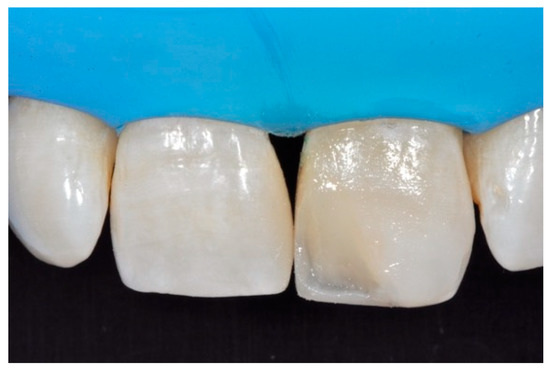

A wise balance of these opaque and translucent shades represents the key factor in obtaining reliable esthetic outcomes and great attention should be paid for their correct positioning [10,27]. Nevertheless, it happens that, during the restorative procedures, some inaccuracies could be made resulting in having opaque shades in place of translucent ones. This is generally realized too late, after finishing and polishing procedures thus compromising the final esthetic result [25]. In Figure 58 in fact the esthetic outcome of the left central incisor could have been improved if the opaque incisal margin had been made thicker and festooned. Conversely, we can notice from Figure 59 excessive thickness in the opaque incisal margin that, if not reduced, could provide an unpleasant final esthetic result.

Figure 58.

A more accurate management of the frame could have improved the thin and not festooned incisal opaque margin on left central incisor.

Figure 59.

Completing the restorations without previously reducing the incisal frame could provide an unpleasant final esthetic outcome.